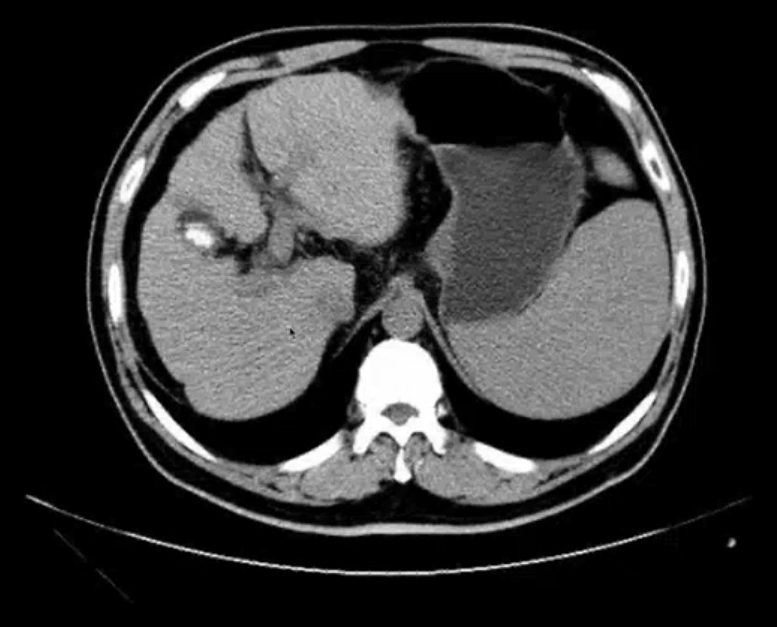

肝CT

- 40~60HU,高于胰,脾

- 肝内管道系统(胆管,肝动脉静脉和门静脉)低于实质,周围小分支多不显示。大血管呈低密度树状影

疾病

- 肝硬化:肝功不全,门脉高压

- 门脉高压:容易形成血栓

- 门静脉直径超15mm

- 伴随脾脏增大

- 脾脏横向超过5个肋单元